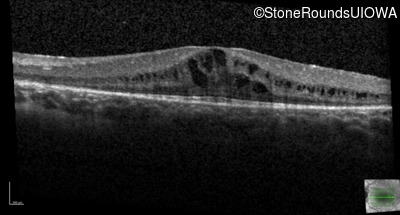

Optical Coherence Tomography - Right - 20/25 -2

Exemplar / OCT Stack

Optical Coherence Tomography - Left - 20/32